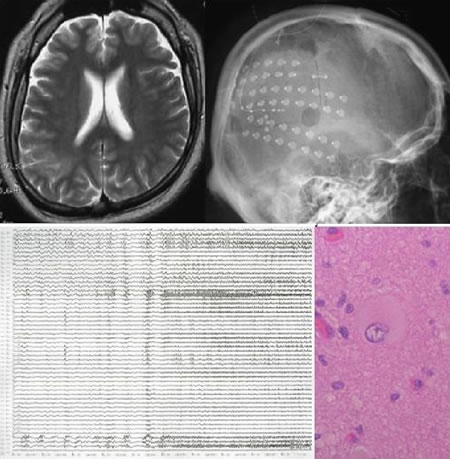

「難治性てんかんの画像と病理」柳下 章 / 新井 信隆定価: ¥ 6000書き込み、折れございません#柳下章 #柳下_章 #新井信隆 #新井_信隆 #本 #自然/医療・薬学・健康